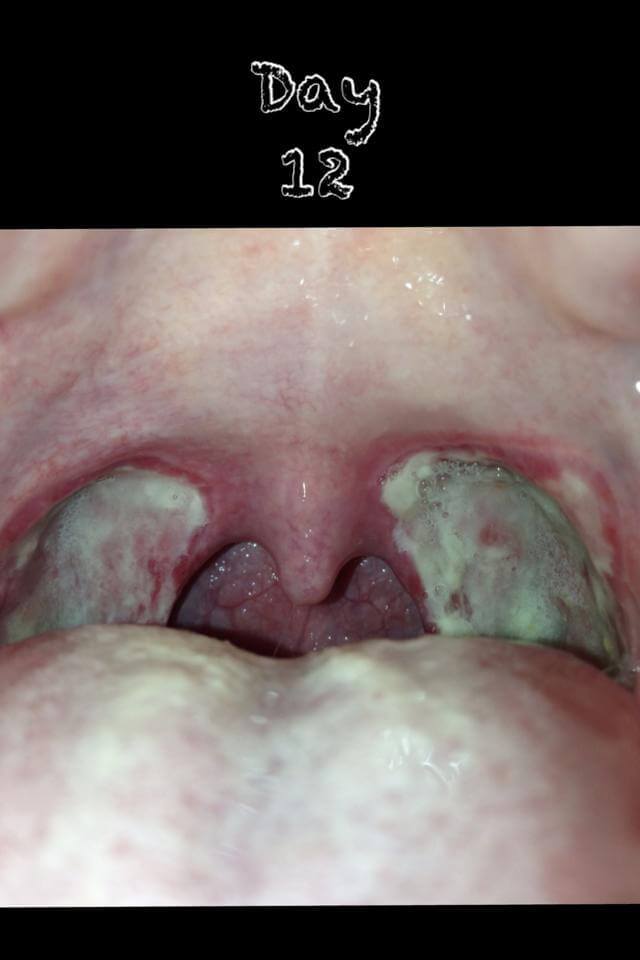

Tonsillectomy Day 8 | Planning and Tonsillectomy Recovery

tonsillectomy scabs pulled out, after tonsillectomy scabs coming off, tonsillectomy recovery scabs falling off, tonsillectomy scabs coming off, tonsillectomy scabs fallen out, tonsillectomy scabs day 4, tonsillectomy scabs and healing